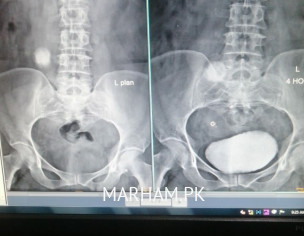

Asking For Mother, Female 45, peshawar

Main ny IVU test report attach ki hai kindly URALOGIST apna opinion de operation k baghair ye stone problem solve ho sakta hai ya operation lazmi karni hogi.. thanx

1) IVU is not a good quality. You got to do CT pyelogram from some decent place for proper diagnosis 2) First need to see if kidney is really functioning or not. 3) Better to start with online video consultation then we can discuss more about it.

CT KUB Plain krwaen

stone bara hai, operation krwana hoga

IVU is very old (2009). Kindly do 3D CTU from a good Hospital n then share.